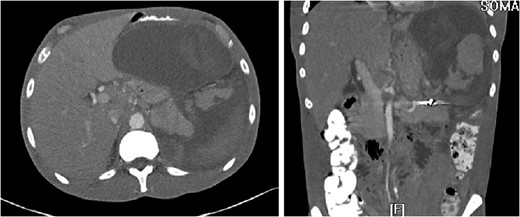

The ‘Islands’ of preserved spleen lit up with IV contrast surrounded by a large collection of old blood and devitalized tissue.